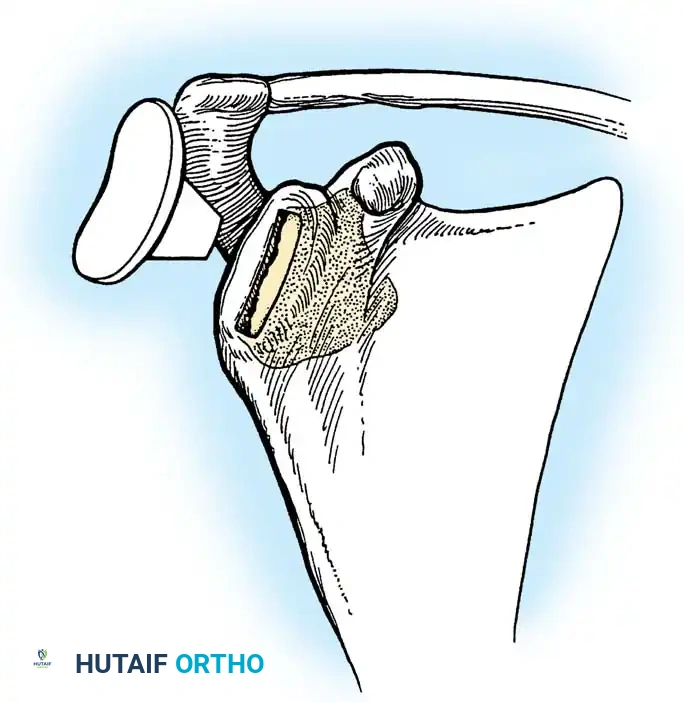

The rTSA fundamentally alters shoulder biomechanics. By medializing and distalizing the center of rotation, it increases the deltoid moment arm and recruits more anterior and posterior deltoid fibers for elevation, bypassing the need for a functional rotator cuff.

Clinical Pearl: Tensioning is the most critical step in rTSA. The joint should be stable in all planes. If the joint dislocates easily, a thicker polyethylene insert or a larger glenosphere is required. However, over-tensioning can lead to acromial stress fractures or brachial plexopathy.

- Scapular Notching (rTSA): Mechanical impingement of the humeral component against the inferior scapular neck during adduction. Minimized by inferior placement and tilt of the glenosphere.